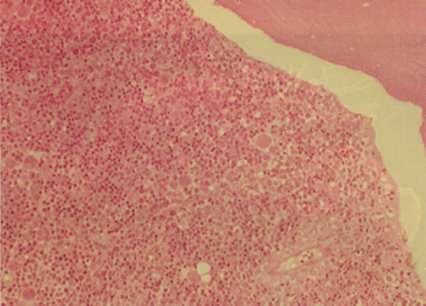

Kemik iliği hasta yüzükoyun yatarken bel kemiğinin iki yan taraflarındaki leğen kemiği delinerek alınır. Burada kemik iliği örneği bel kemiğinden değil ona bitişen leğen kemiğinden alınmaktadır. Önce özel Maçlarıyla cilt temizliği yapılır. Daha sonra kemik iliğinin alınacağı bölgede kemik (üzerini örten ve periost diye bilinen zarı) bir anestetik madde zerk edilerek uyuşturulur. Bu işlemlerden sonra kalınca özel bir iğne kemik içine sokulur ve iliğin olduğu yere kadar ilerletilir. İğne yerine gelince bir enjektör yardımıyla ilik dokusu emilir (aspirasyon). Çekilen ilik, lam denen bir cam üzerine yayılır, kuruduktan sonra özel boyalarıyla boyanıp mikroskop altında incelenebilir. Kemik iliği aspirasyonuyla kan yapan kök hücreler ve bunlardan oluşmakta olan değişik olgunlaşma evrelerindeki kan hücreleri incelenebilir. Bu işlemi yapmakta kullanılan iğne, iliğin içinde ilerletilirse ilik dokusu iğnenin içine girer. İğneye çeşitli hareketler verilerek iğne içindeki ilik dokusunun yerinden kopması sağlanabilir. Daha sonra, çıkarılan iğnenin içinde kalan ilik dokusu, özel ilaçlı sıvısı içinde değişik işlemlerden geçirilerek kesitler alınıp boyanarak tetkik edilir. Bu işleme kemik iliği biyopsisi denir ve hematolojik patoloji konusunda uzmanlaşmış patologlar tarafından değerlendirilir. Kemik iliği biyopsisi kök hücreden kan yapımını kemik iliği stroması içinde değerlendirir. Yani biyopsiyle aspirasyonun yeri ve kıymeti farklıdır. Bu nedenle çoğu kez daha geniş bilgi için bu iki işlem aynı anda yapılır.

Kemik iliği aspirasyonu cam üzerine yayılıp, özel boyalarla boyanarak mikroskop altında değerlendirildiğinde kemik iliğinde yer alan en genç ve olgunlaşmamış hücrelerden, giderek olgunlaşmış olanlar ve kan dolaşımına katılmaya hazır hale gelmiş hücrelere kadar bütün hücreleri görmek mümkündür. Hematologlar kemik iliğindeki bu hücreleri görünümlerinden (morfoloji) tanırlar. Hangi hücrenin sonunda hangi hücreyi oluşturmak üzere hangi olgunlaşma evresinde hücre olduğu tanınır. Normal koşullarda yürüyen bir kan yapım süreci (hematopoie-sis) içinde genç, olgunlaşmakta olan hücrelerin oranlarında değişiklikler (azalmalar ya da çoğalmalar) ya da hücrelerin görünümlerinde normale göre sapmalar olması hastalık olarak kabul edilir. Hücre görünümleri normal olduğu halde özellikle oransal değişiklikler olması hali bazı zorlanmalar halinde gelip geçici olarak ve durumu kurtarmak için oluyorsa bu durum hastalık değildir. Örneğin bir kanama ya da kan bağışı sonrasında kemik iliğinde eritrosit yapan genç

Kemik iliği biyopsileri kemik iliğinde kan yapımına katılan hücre oranını değerlendirmekte ve kemik iliğinin stromasıyla kan yapımında olan hücrelerin birbirleriyle etkileşimleri ve orantısal dağılımları için bilgi verir.